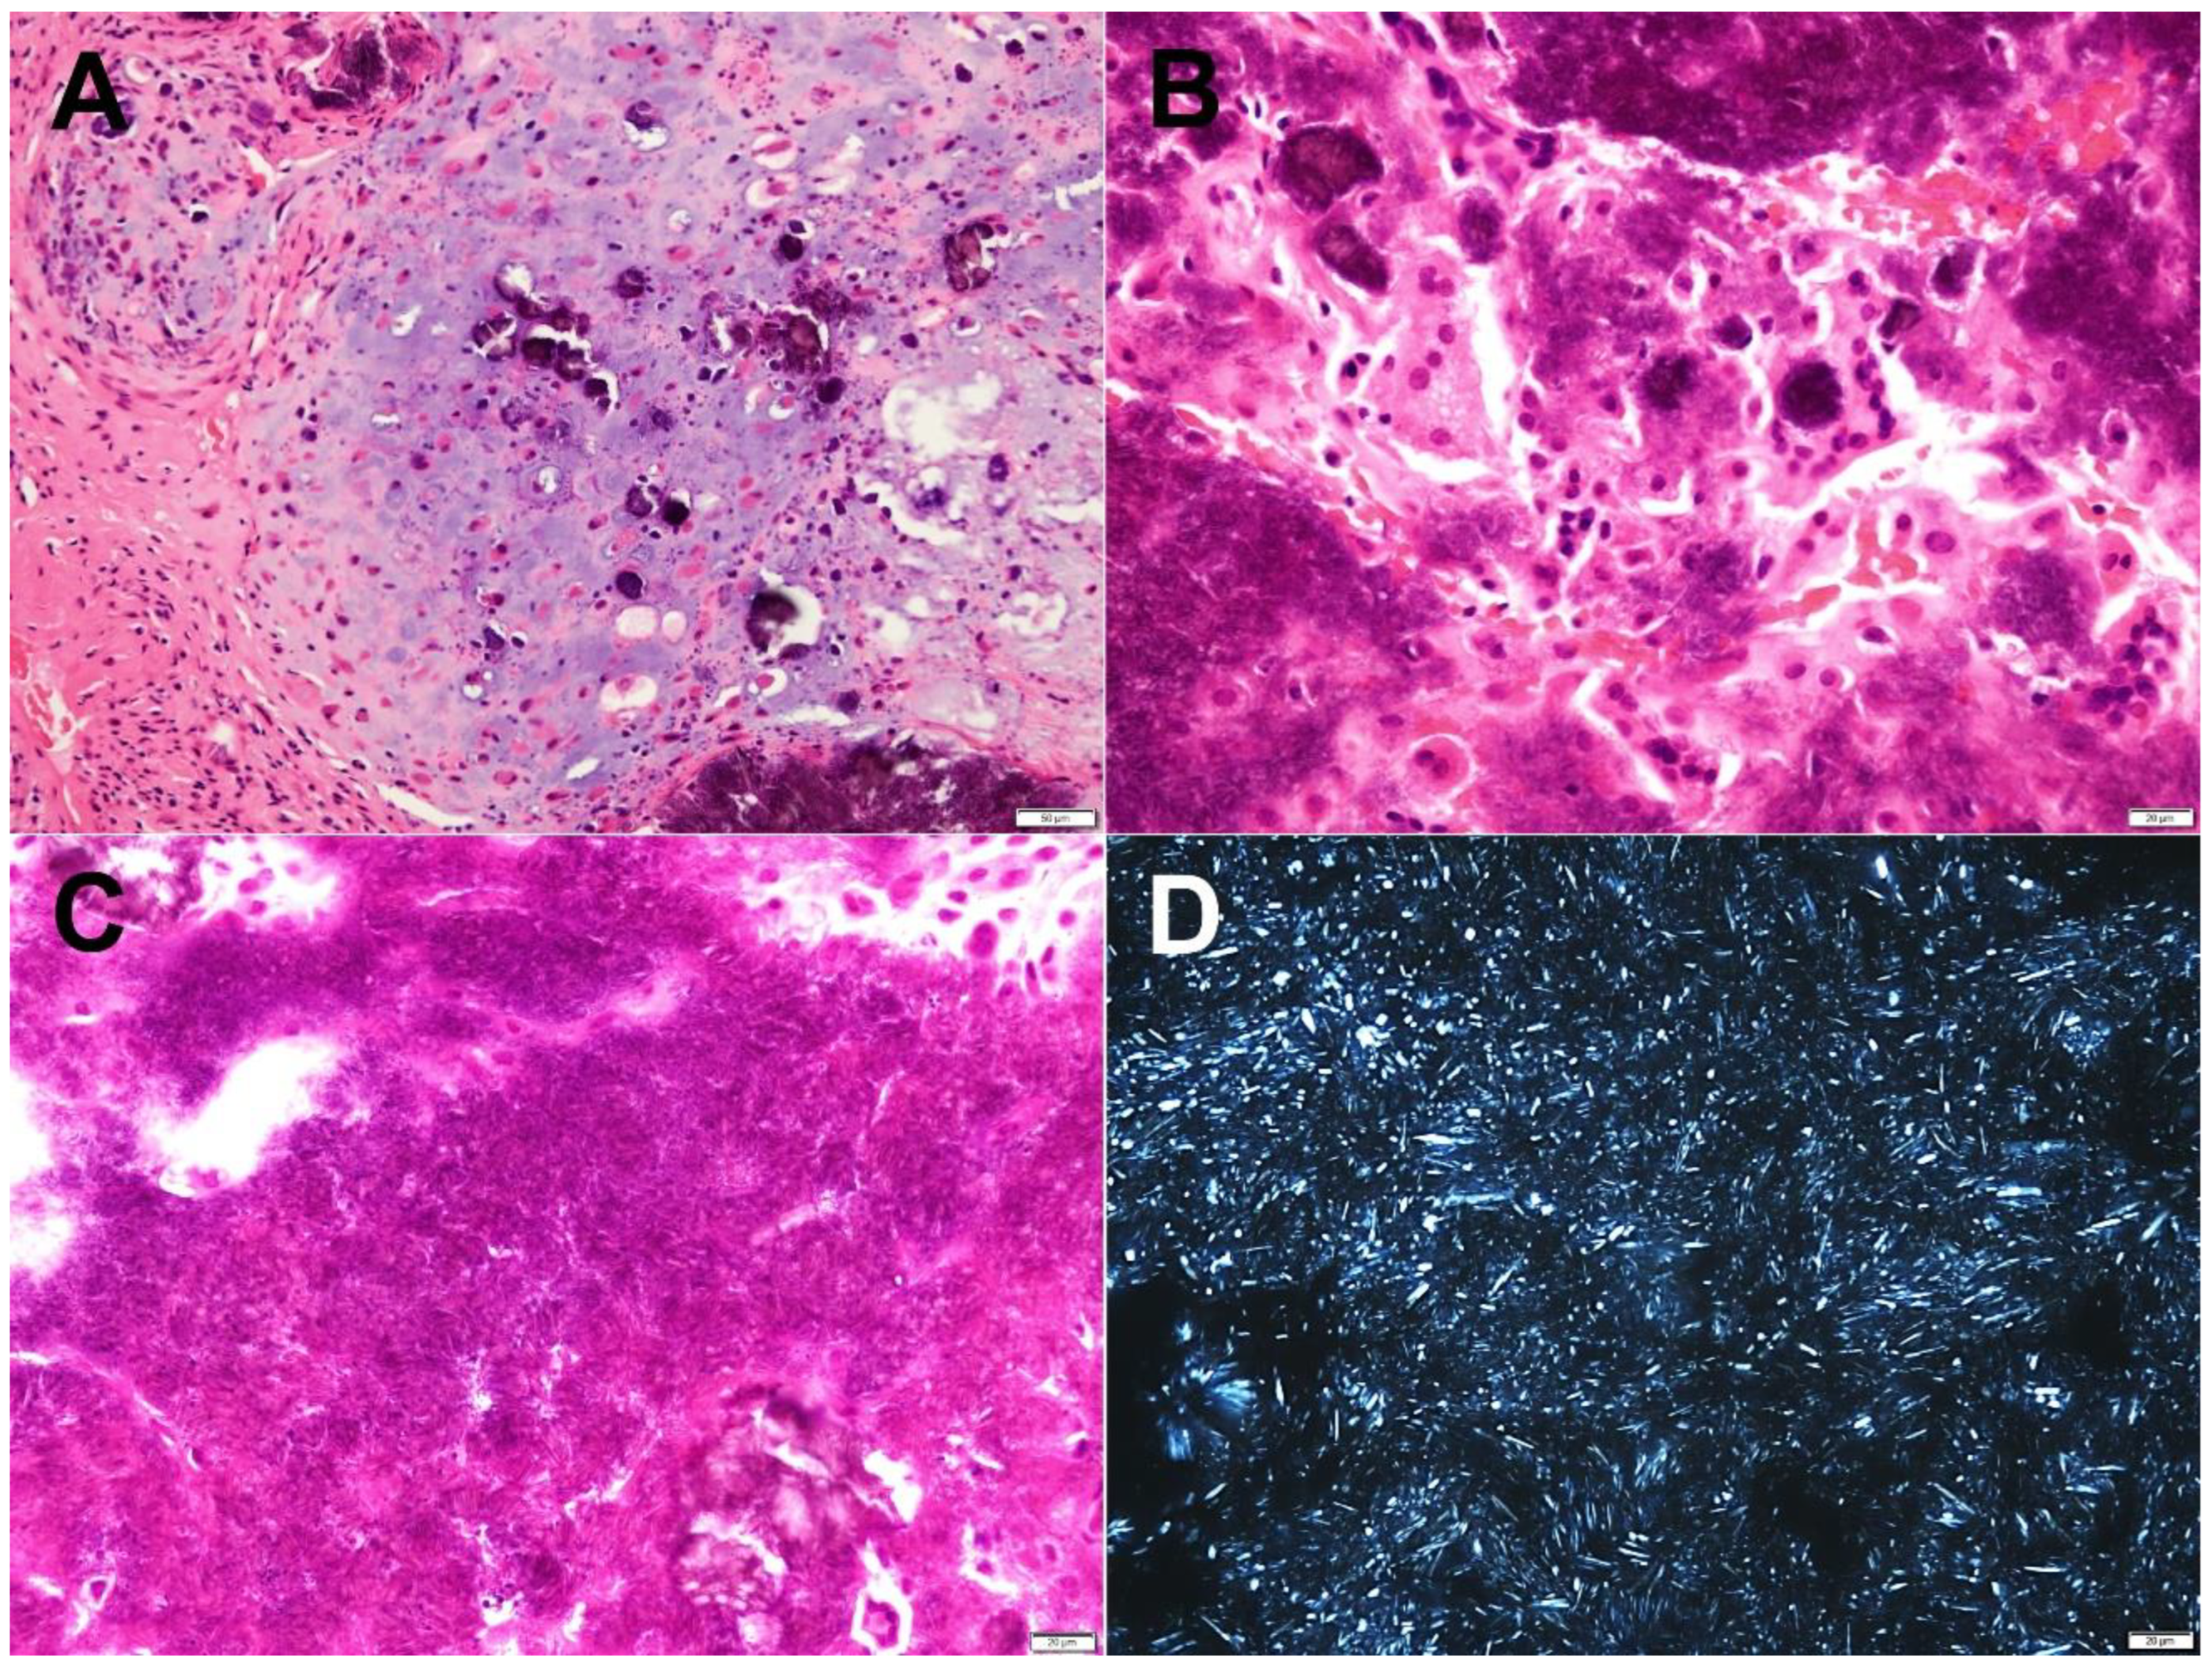

2.2. Pathological Findings